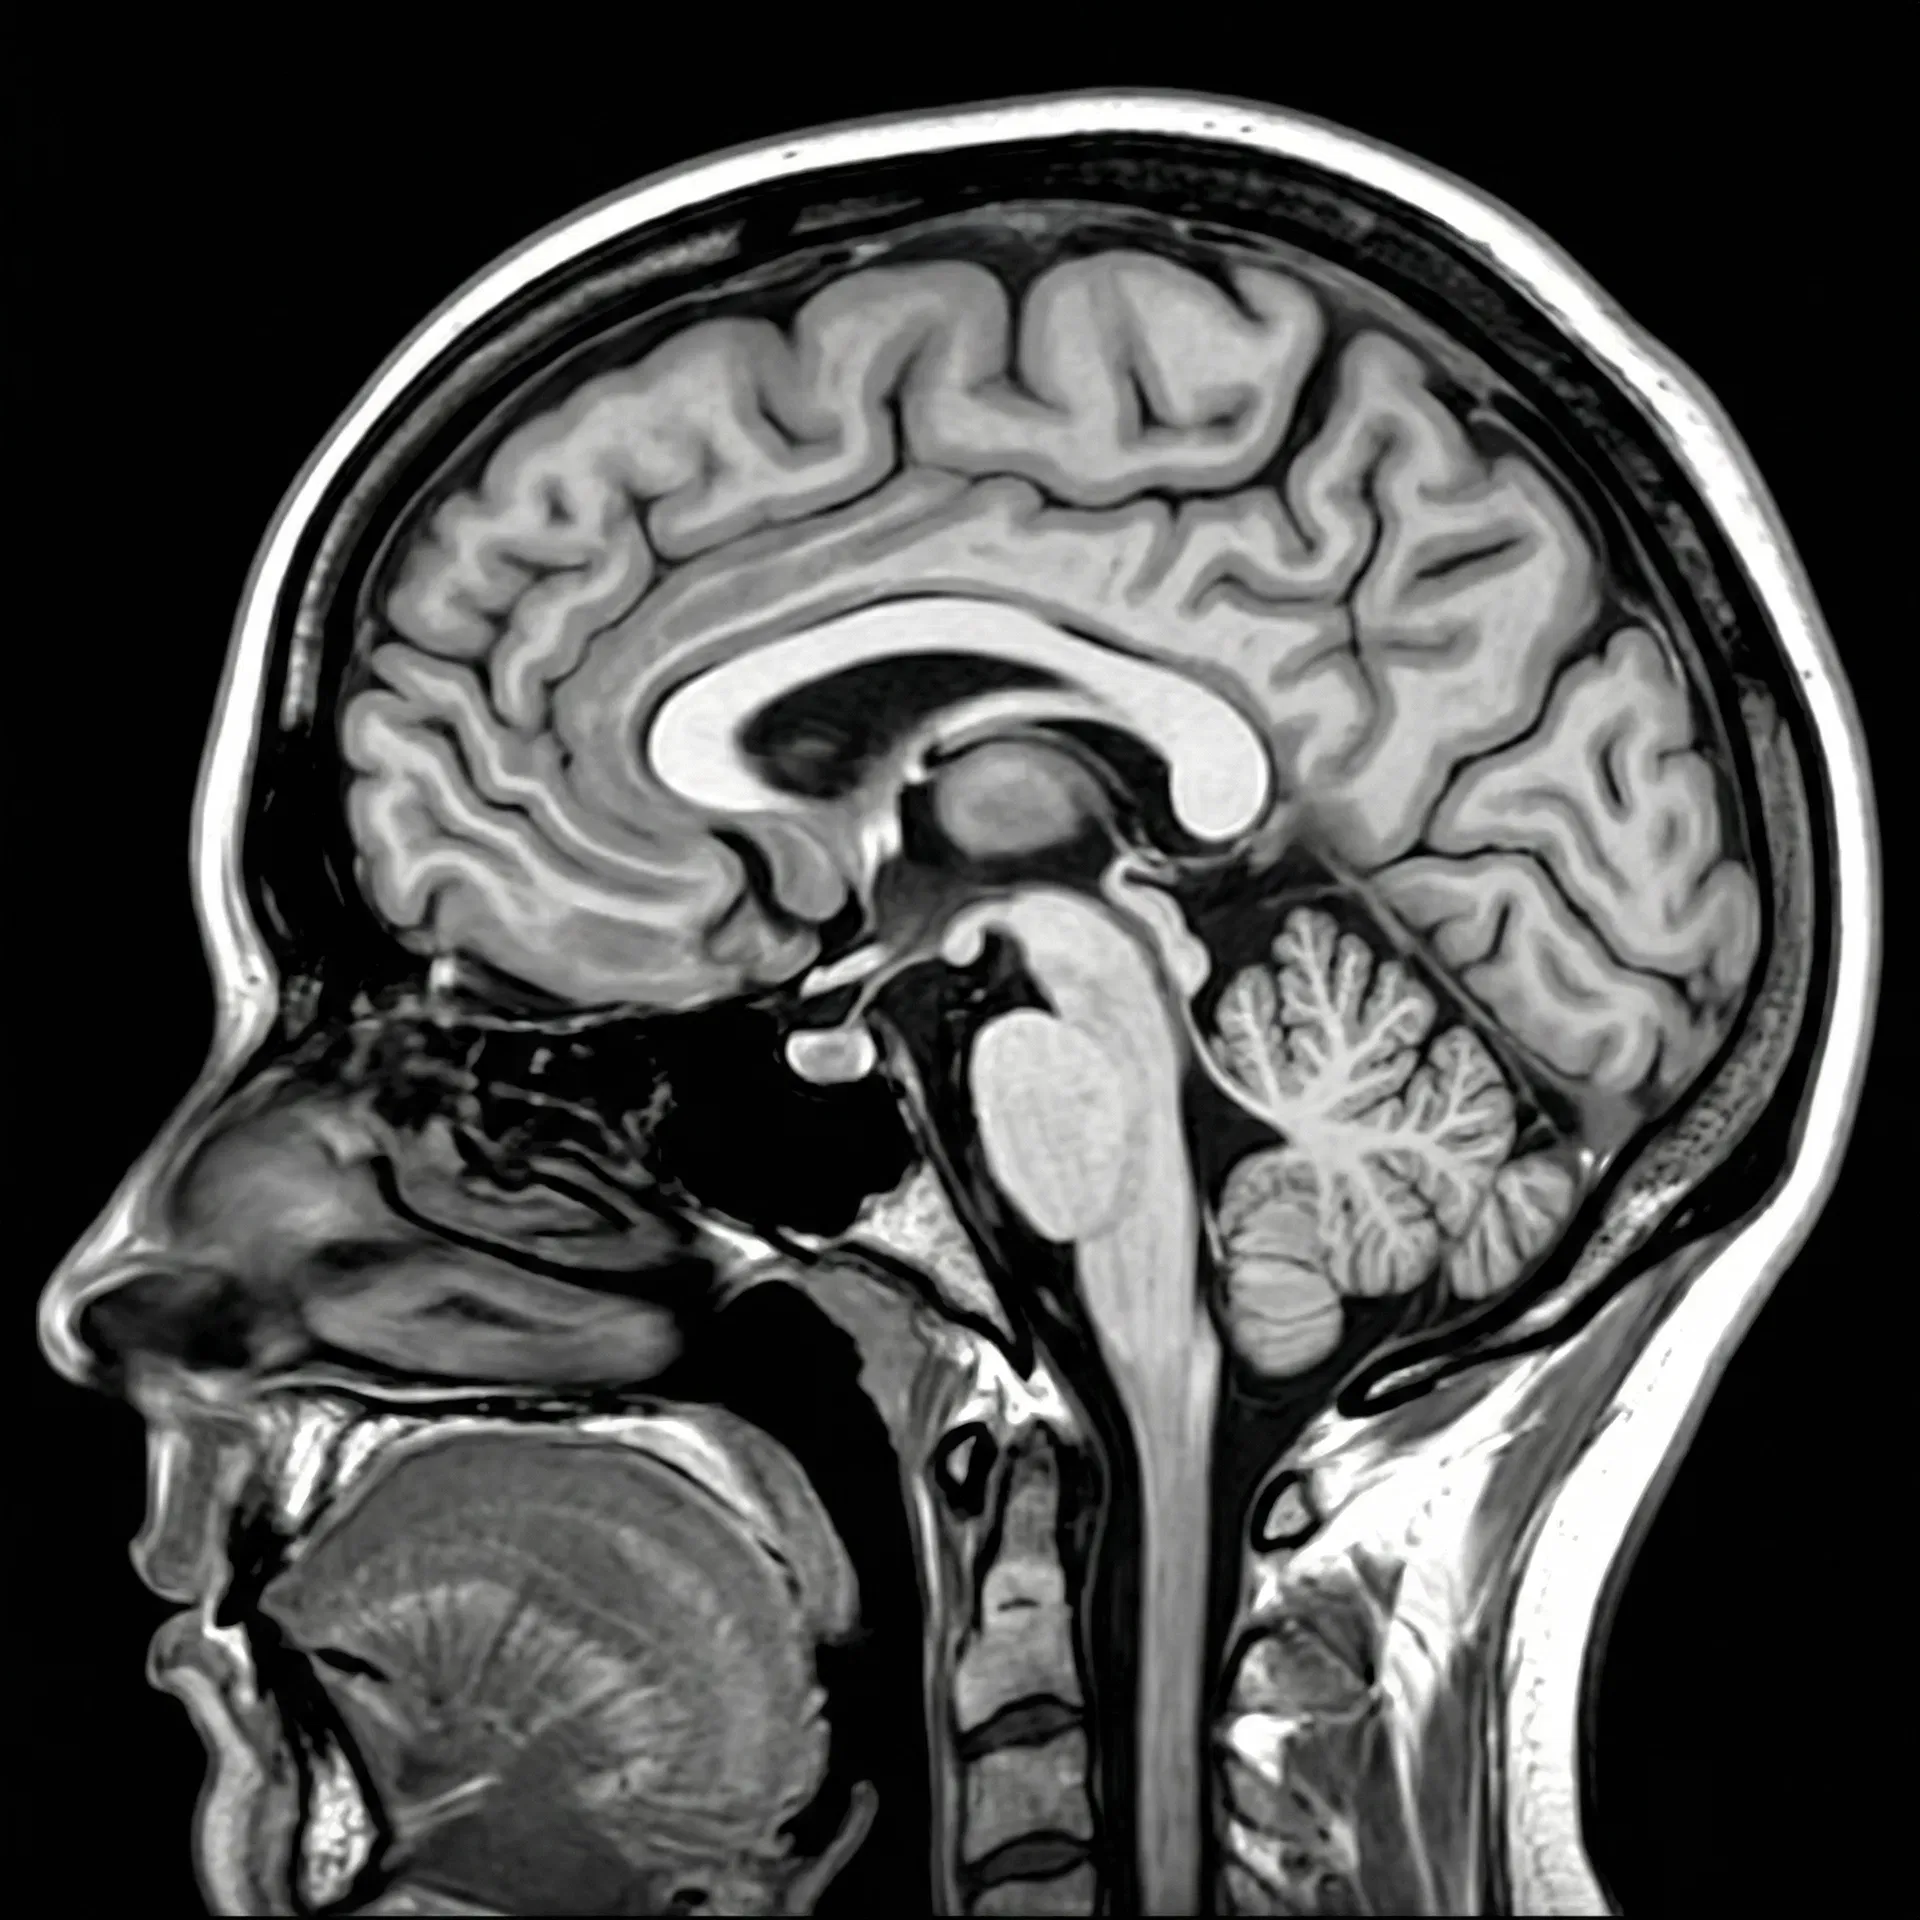

Structural MRI and PET scans of the female brain, revealing the neuroanatomical and metabolic patterns central to Alzheimer's research.

Structural MRI — Sagittal View

Female brain, T1-weighted imaging